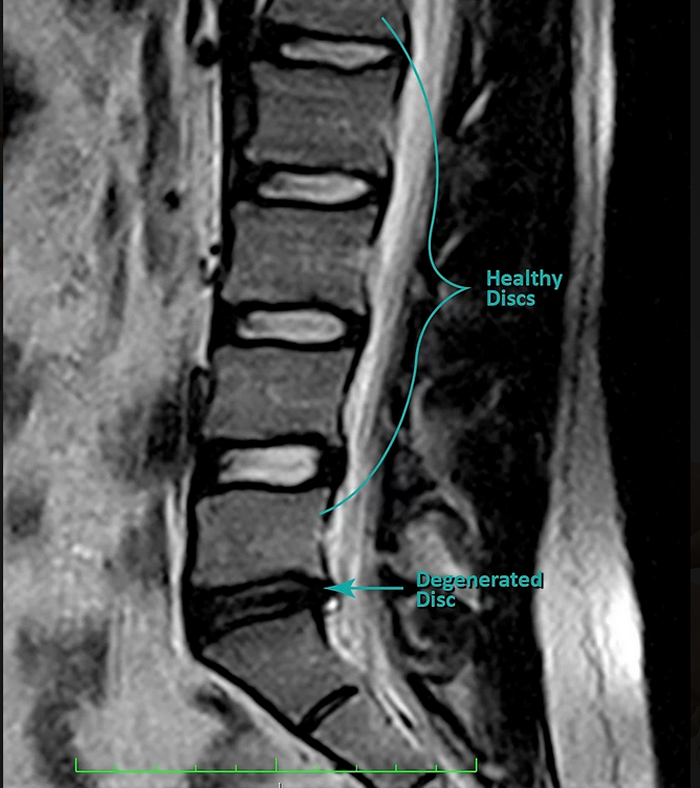

Degenerative disc changes are often characterized by a loss of water content in the disc (confirmed using a T-2 weighted MRI sequence — see Figure 4) and various changes to its elastic and mechanical properties. This can lead to dLBP. It is important to note that although degenerative changes may be observed, the pain may be unremarkable. Conversely, imaging may reveal very mild degenerative changes, yet the patient may be experiencing significant pain.